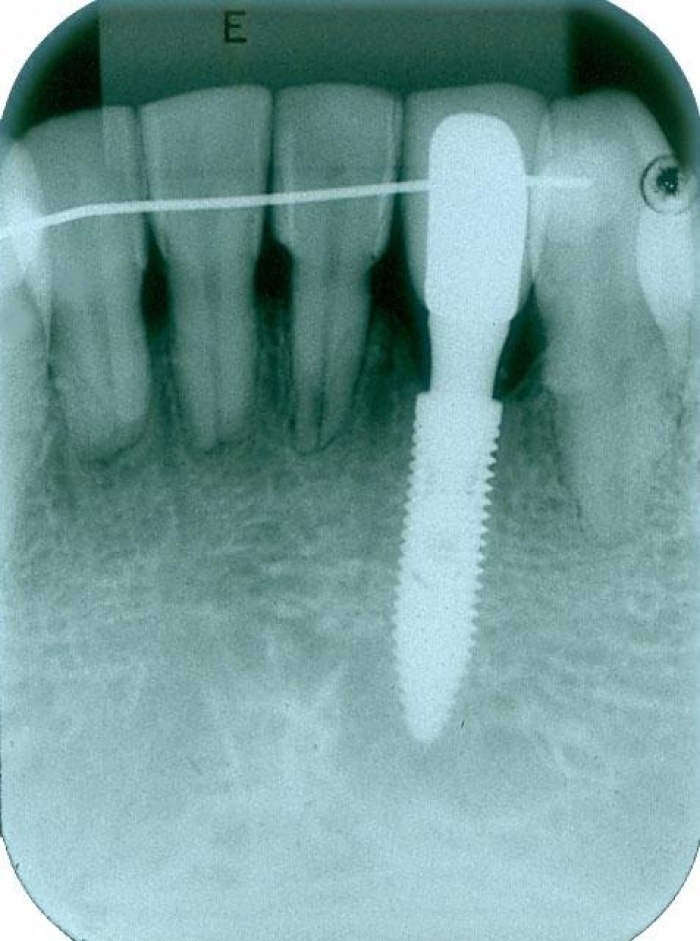

Raio X com próvisório já instalado sobre o implante cone morse

Raio X de controle, realizado 05 meses após o término do tratamento